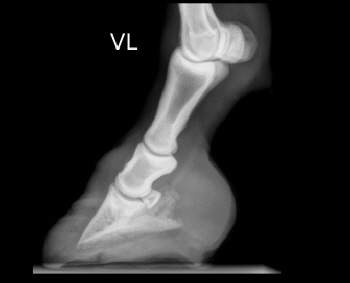

Röntgenbilder akuter- und chronischer Hufrehehufe vorher und nachher

Nachstehend stellen wir einige Röntgenbilder von Hufrehepferden ins Netz, welche das Vorher und das Nachher zeigen. Wir möchten damit aufzeigen, dass durch eine richtige Hufbearbeitung ein Hufbein wieder in eine korrekte Lage innerhalb der Hornkapsel zu liegen kommen kann.

In besonders schweren Fällen wurde doch zumindest eine Optimierung angestrebt.

nachher